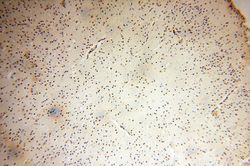

Immunohistochemistry

14574-1-AP IHC

Full details

Method: